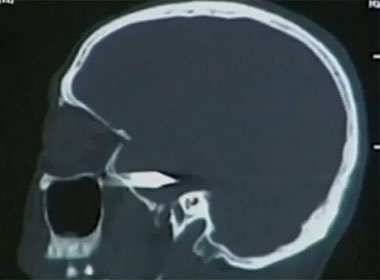

Các bác sĩ sau đó đã dùng biện pháp hút giòi và dùng máy quét não để kiểm tra xem những con ấu trùng này đã tấn công vào não bộ hay chưa. Thật may mắn là những con ấu trùng ăn thịt này chưa kịp tấn công não, nhưng chúng đã nhai mất một mảnh thịt ở trong lỗ tai có kích thước 12mm.